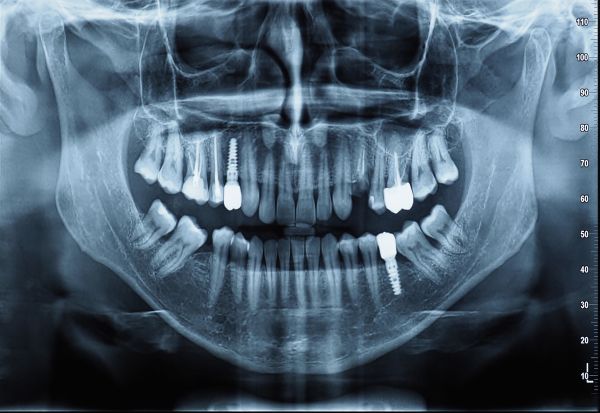

Античките и средновековните човечки останки покажуваат дека кариесот, стоматолошките апсцеси и воспаленијата што се ширеле низ телото често доведувале до тешки заболувања, па дури и смрт долго време пред современата стоматологија да развие ефикасни третмани. И денес, дури и Светската здравствена организација го препознава влошувањето на оралното здравје како сериозен проблем кај повозрасните лица.

Истражувачи од Универзитетот во Осака во Јапонија анализирале здравствени и стоматолошки податоци на речиси 200.000 лица на возраст од 75 години и утврдиле дека оние со повеќе изгубени или расипани заби имаат зголемен ризик од смртност во споредба со лицата со здрави или пломбирани заби, потврдувајќи ги наодите од претходни истражувања.

Истражувачите наведуваат дека бројот на заби е важен показател за оралното здравје. Мал број на постојни заби е поврзан со низа здравствени проблеми, меѓу кои губење телесна тежина, дијабетес, хипертензија, кардиоваскуларни заболувања, терминална бубрежна болест, деменција, рак и зголемена смртност.

Со цел да се утврди влијанието и на бројот и на состојбата на забите, тимот од Осака ги следел испитаниците во период од 3-4 години. Забите биле класифицирани како здрави, пломбирани или расипани. Најсилна поврзаност со понизок ризик од смртност била утврдена кај лицата со поголем број здрави и пломбирани заби, додека повеќето починати испитаници имале изгубени или расипани заби.